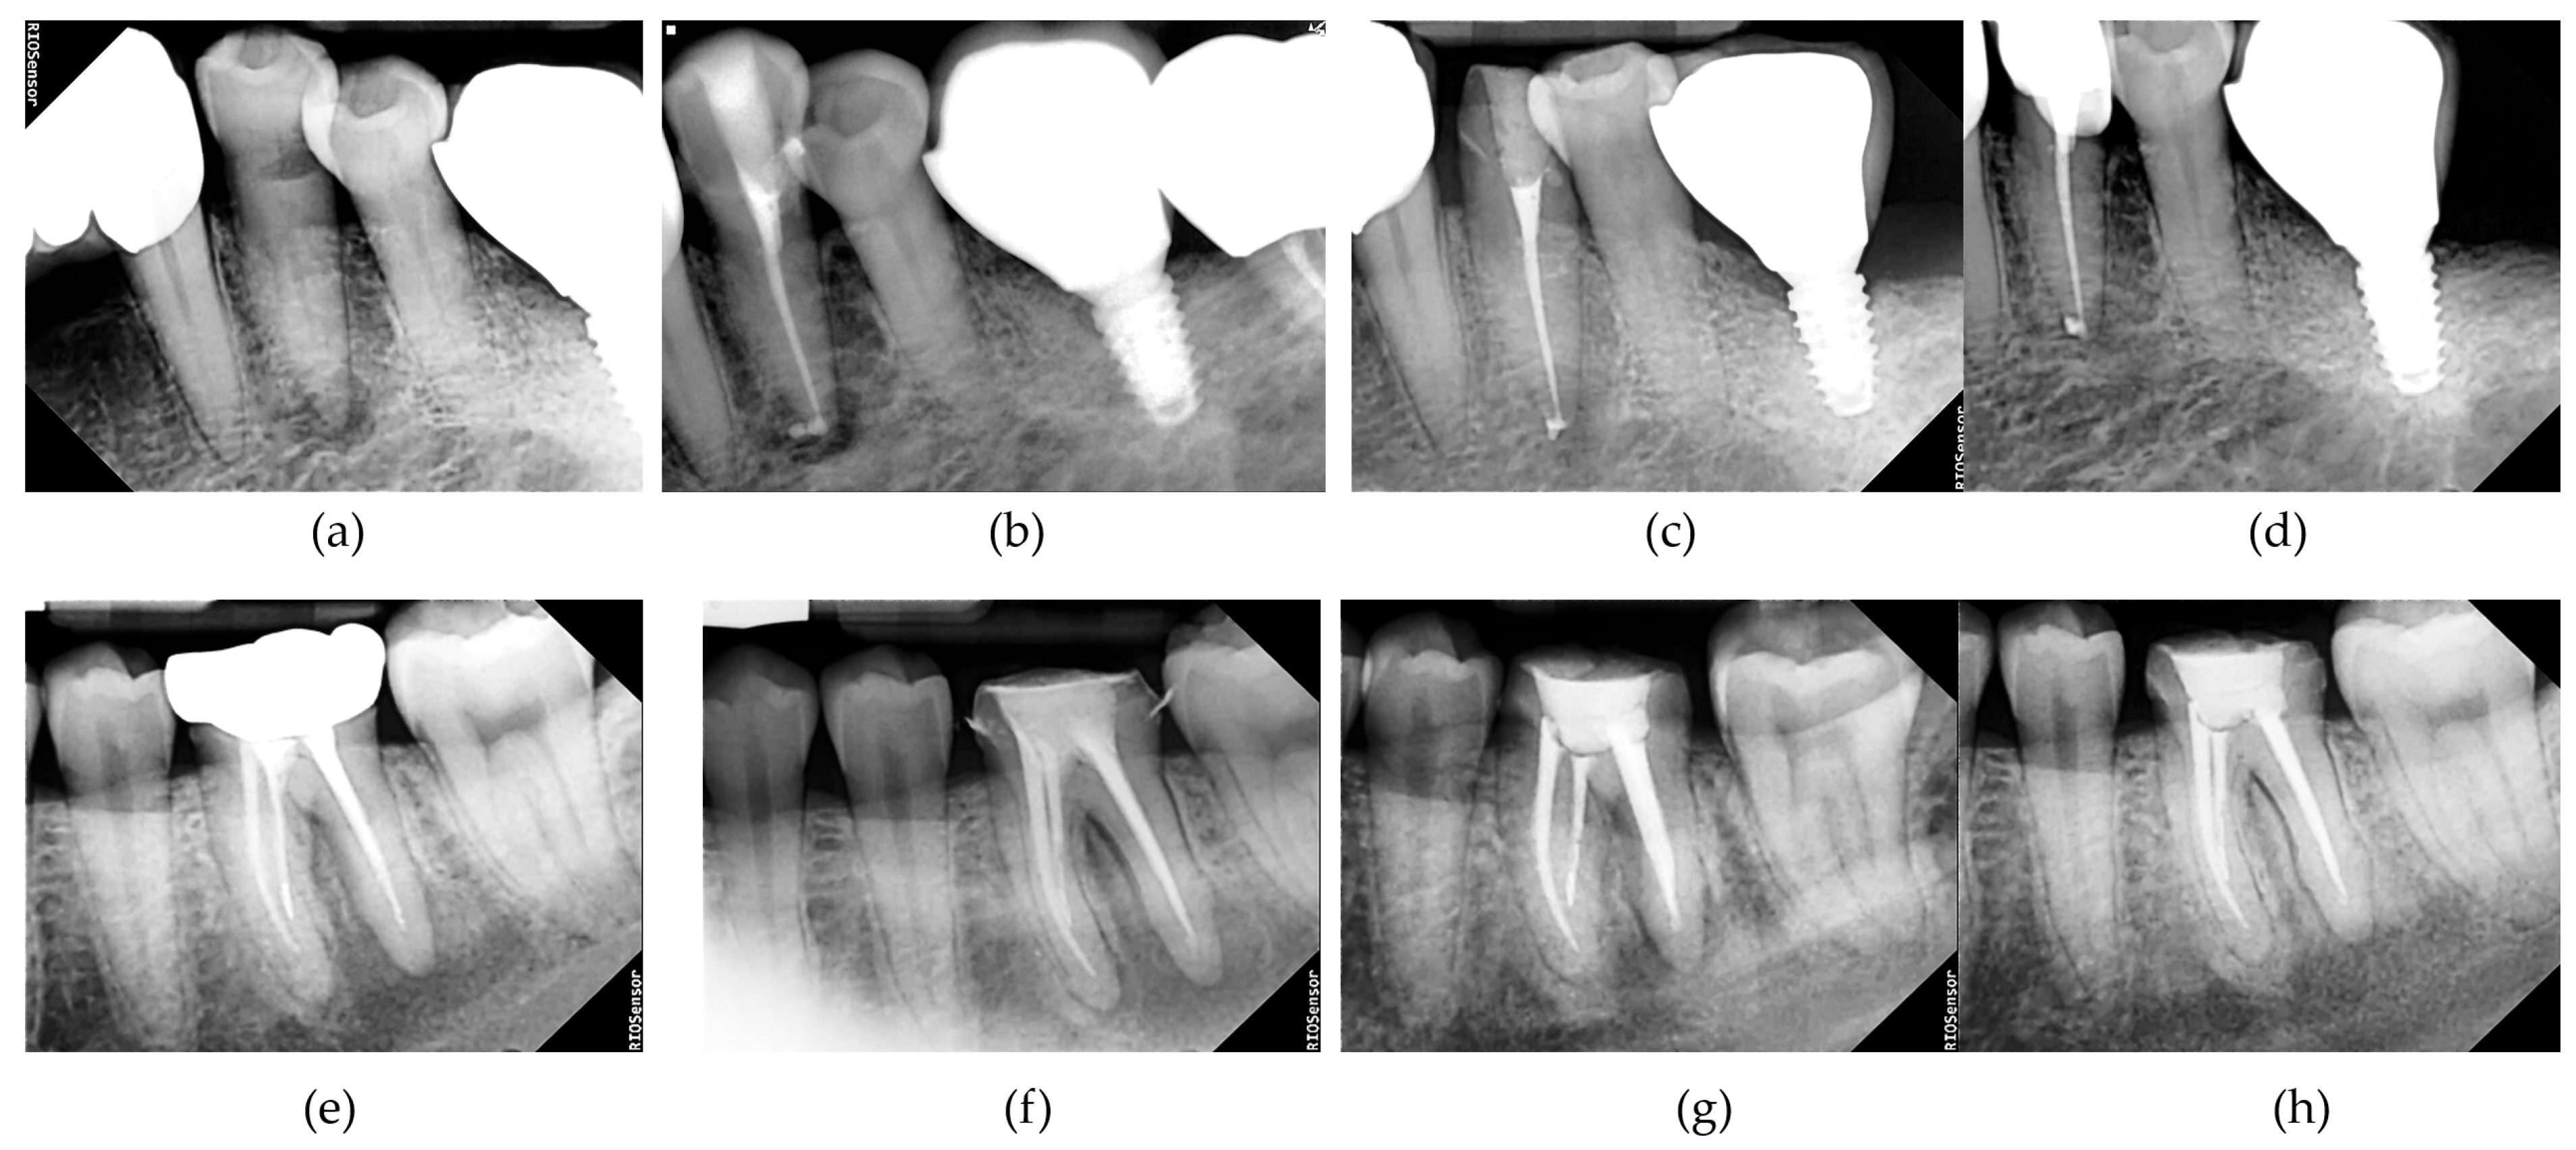

Radiographs were independently evaluated by two board-certified oral and maxillofacial radiologists who were blinded to group allocation. The Periapical Index (PAI) scoring system was used to assess periapical healing [24]. Additional radiographic examples were provided to the reader to assist in interpreting the radiographic images of the teeth (Figure 1).

Figure 1. Representative radiographic images with corresponding Periapical Index (PAI) scores. The images depict various degrees of periapical radiolucency, assessed according to the PAI scoring system, introduced by Ørstavik et al. [24], ranging from a healthy periapical status (score 1) to severe periodontitis with exacerbating features (score 5). These reference images were used to assist the blinded radiologists in evaluating periapical healing in this study.